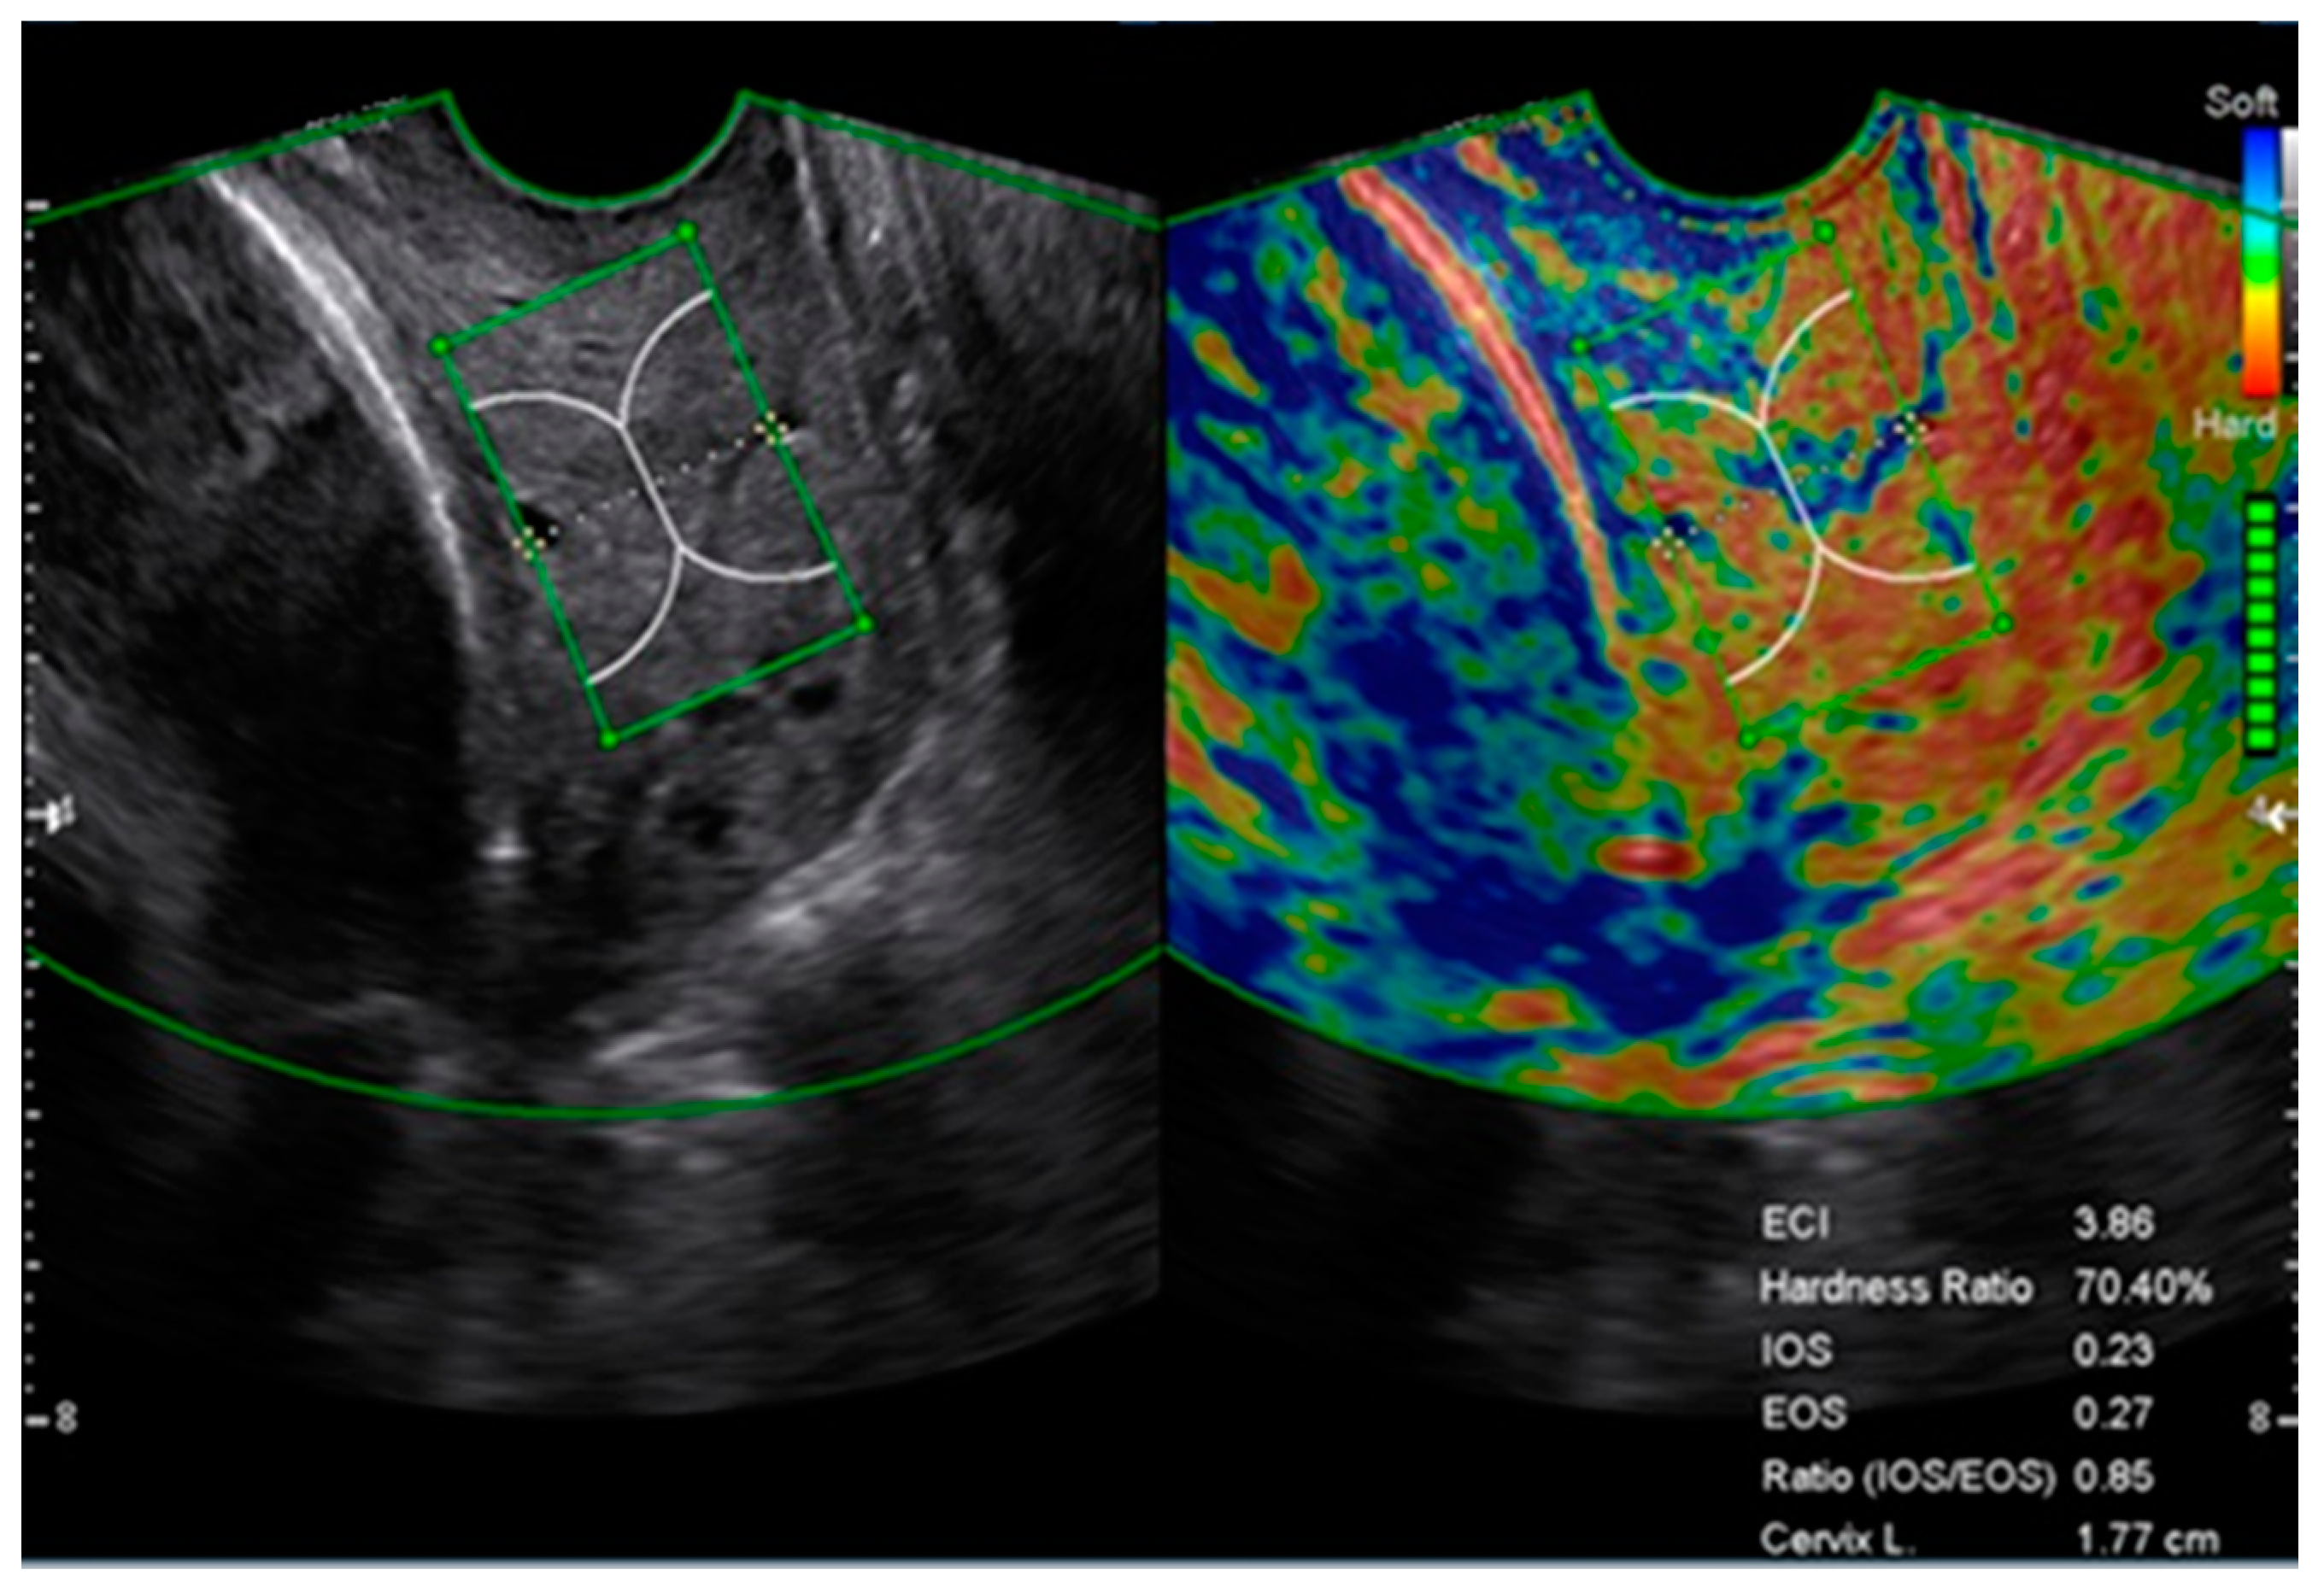

2.2. Cervical Length and Elastography Measurement

- Seol, H.J.; Sung, J.H.; Seong, W.J.; Kim, H.M.; Park, H.S.; Kwon, H.; Hwang, H.S.; Jung, Y.J.; Kwon, J.Y.; Oh, S.Y. Standardization of measurement of cervical elastography, its reproducibility, and analysis of baseline clinical factors affecting elastographic parameters. Obstet. Gynecol. Sci. 2020, 63, 42–54. [Google Scholar] [CrossRef] [PubMed]

| IOS | 0.22 ± 0.07 | 0.30 ± 0.09 | 0.001 | 0.23 ± 0.08 | 0.34 ± 0.09 | 0.002 |

| EOS | 0.26 ± 0.09 | 0.32 ± 0.08 | 0.063 | 0.26 ± 0.08 | 0.35 ± 0.09 | 0.018 |

| ECI | 3.19 ± 1.09 | 4.00 ± 1.23 | 0.037 | 3.09 ± 0.95 | 4.03 ± 0.58 | 0.020 |

| HR | 73.19 ± 14.77 | 61.17 ± 12.74 | 0.020 | 72.29 ± 15.40 | 53.24 ± 14.98 | 0.004 |